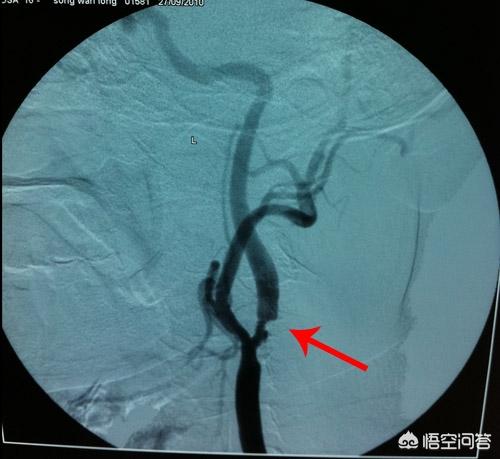

頸動脈が閉塞して狭くなっているのか、プラークが形成されているのかを知るには、経験豊富な医師が聴診器で聴けばわかる。 頸動脈が狭くなっていれば、血液が通過するときの雑音が聞こえることが多い。加えて頸動脈の超音波検査は、頸動脈のアテローム斑の存在と狭窄の程度を検出する便利で信頼できる安価な方法である。もちろん、動脈造影は狭窄を診断するための "ゴールド・スタンダード "である。

頸動脈図

上の写真によると、我々は明らかに頸動脈は首の非常に重要な血管であることを知ることができ、首の喉頭結節の隣に2本の横指は、そのブールに触れることができ、ちょうど動脈を発行し、総頸動脈と呼ばれ、総動脈の両側は、胸鎖関節の後、気管と喉頭の外側に沿って上方気管と喉頭の外側に沿って平坦に甲状軟骨の上端に、内頸動脈と外頸動脈に分かれている、総頸動脈の頭部、顔面、頸部出血圧迫。

頸動脈閉塞症の病態とその部位

頸動脈血栓塞栓性脳梗塞17例の症例解析(王暁)によると、脳梗塞の引き金となった頸動脈塞栓症の患者17例は男性で、年齢は43歳から83歳、平均年齢は63歳であった。これらの患者には、錯乱1例、四肢脱力12例、視野欠損1例、単眼視力低下1例、めまい1例、ろれつが回らない1例がみられた。

頸動脈塞栓症は、一般に脳神経の局在に関連したさまざまな病的反応を引き起こすことがわかる。 言語不明瞭、視野障害、四肢機能障害など、実際には脳虚血後のさまざまな機能障害は、虚血部位の違いによるものである。